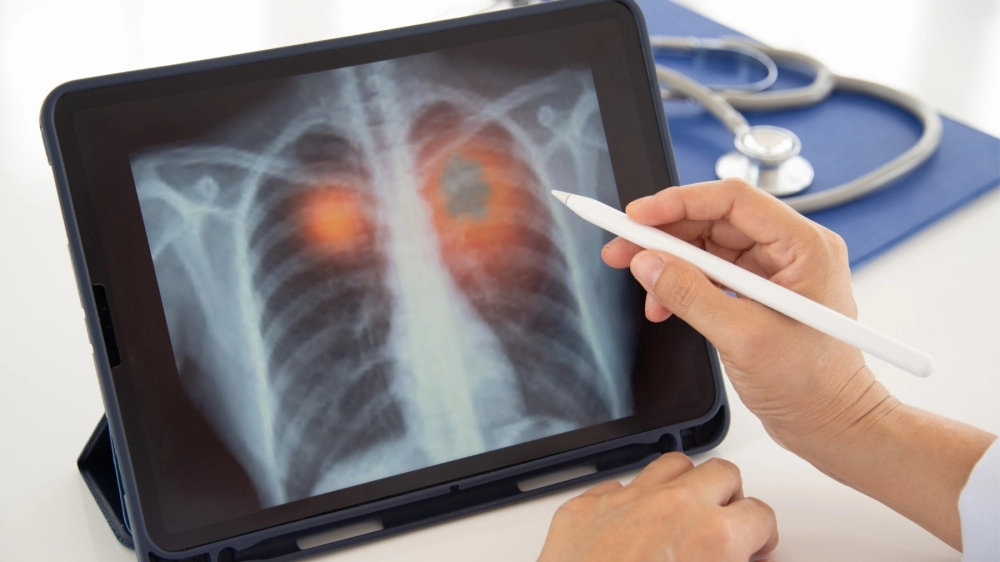

Hình ảnh chụp X-quang phổi của bệnh nhân bị viêm phổi